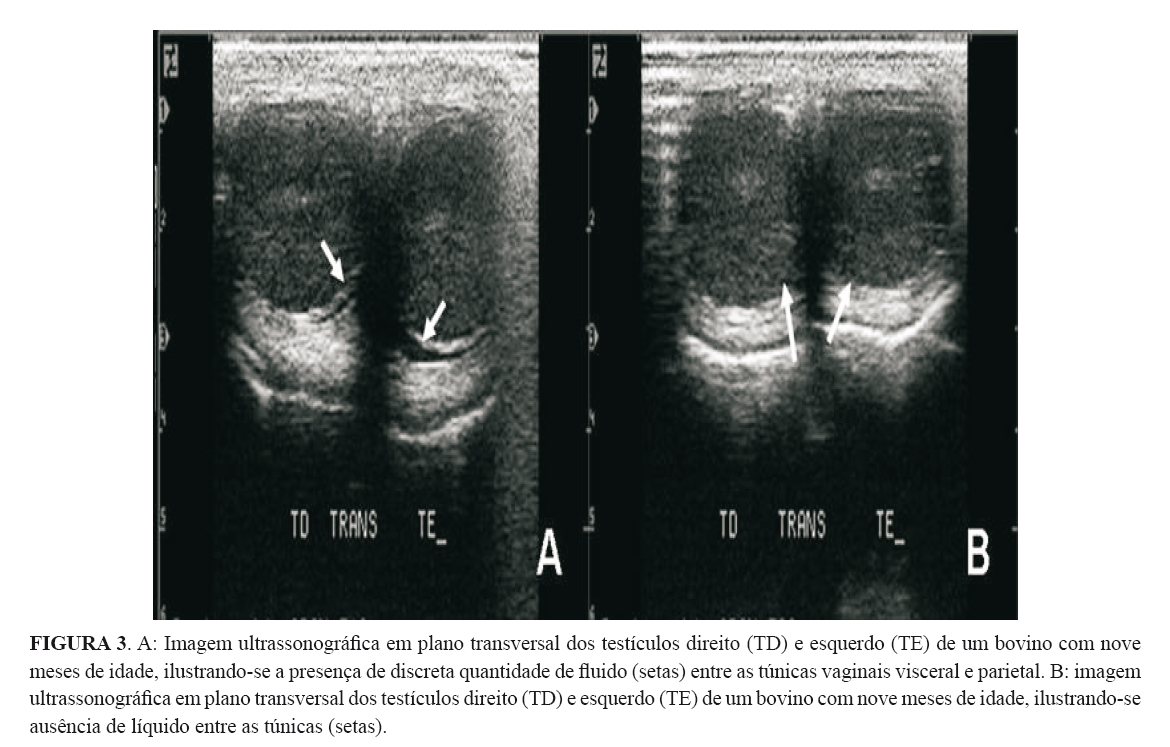

As túnicas testiculares apresentaram-se ao ultrassom como uma linha hiperecoica que circundou todo o parênquima testicular em plano transversal (Figura 3B). As túnicas vaginais somente foram diferenciadas quando havia fluido entre elas, ou seja, a imagem caracterizou-se por uma linha anecoica entre duas linhas hipercoicas, correspondendo, respectivamente, à túnica vaginal visceral e à túnica vaginal parietal (Figura 3A). Tal presença de líquido foi considerada fisiológica e não um processo patológico.

As túnicas somente puderam ser diferenciadas quando havia líquido entre elas, o que foi descrito por PECHMAN & EILTS (1987) e ABDEL-RAZEK & ALI (2005). Segundo PECHMAN & EILTS (1987), a presença de líquido entre as túnicas vaginais parietal e visceral pode ser normal, porém mais de 2 mm de espessura entre as túnicas pode indicar processo patológico. Em alguns animais da raça Nelore foi encontrado líquido entre as túnicas e tal imagem ao ultrassom pôde ser descrita como uma linha anecoica entre duas linhas hiperecoicas (túnica vaginal parietal e visceral), sendo que esta presença de líquido foi considerada fisiológica, já que os testículos apresentavam-se aparentemente normais à palpação e ao ultrassom.